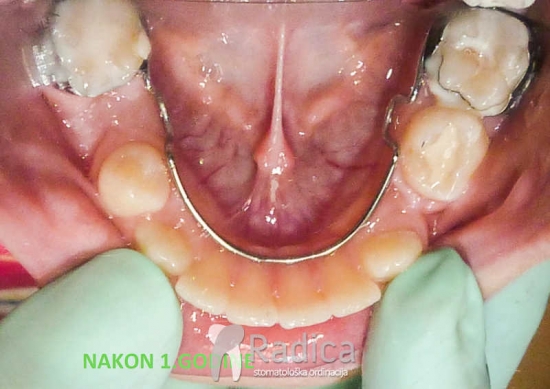

1. Prerani gubitak mliječnih molara. Lingvalnim lukom spriječavamo pomak trajnih molara naprijed.